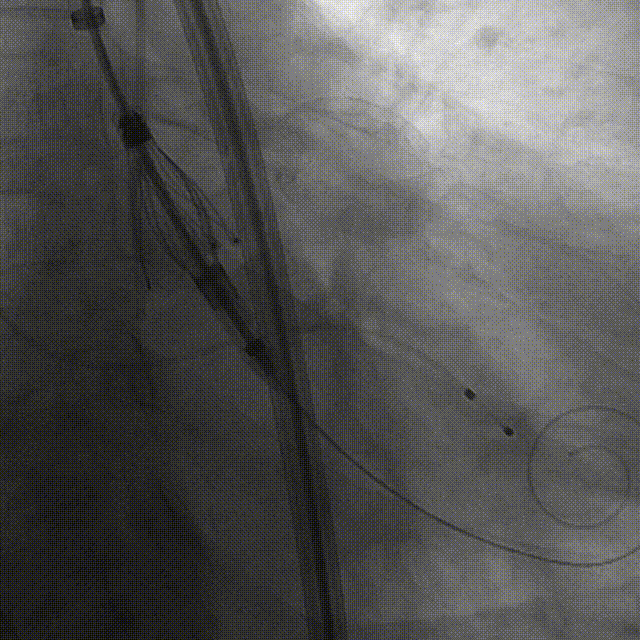

手术过程:5A 标准化流程SOP

右窦中心造影

大鞘到STJ

瓣膜调弯后解离

瓣膜右窦中心调整

定位键窦不对齐

灵活旋转操作

确认窦对齐

入窦